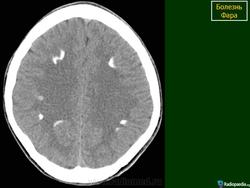

Основным методом прижизненной диагностики болезни Фара является КТ мозга, выявляющая симметричные участки резко повышенной плотности, располагающиеся в указанных выше структурах мозга. Иногда симметричные кальцификаты в виде точечных «вкраплений» могут быть видны на обычных рентгеновских снимках черепа, чаще в супраселлярной области на расстоянии 3-4 см от средней линии. Важно подчеркнуть, что при подозрении на идиопатическую кальцификацию базальных ганглиев важно проводить нейровизуализационное обследование ближайших родственников больного.